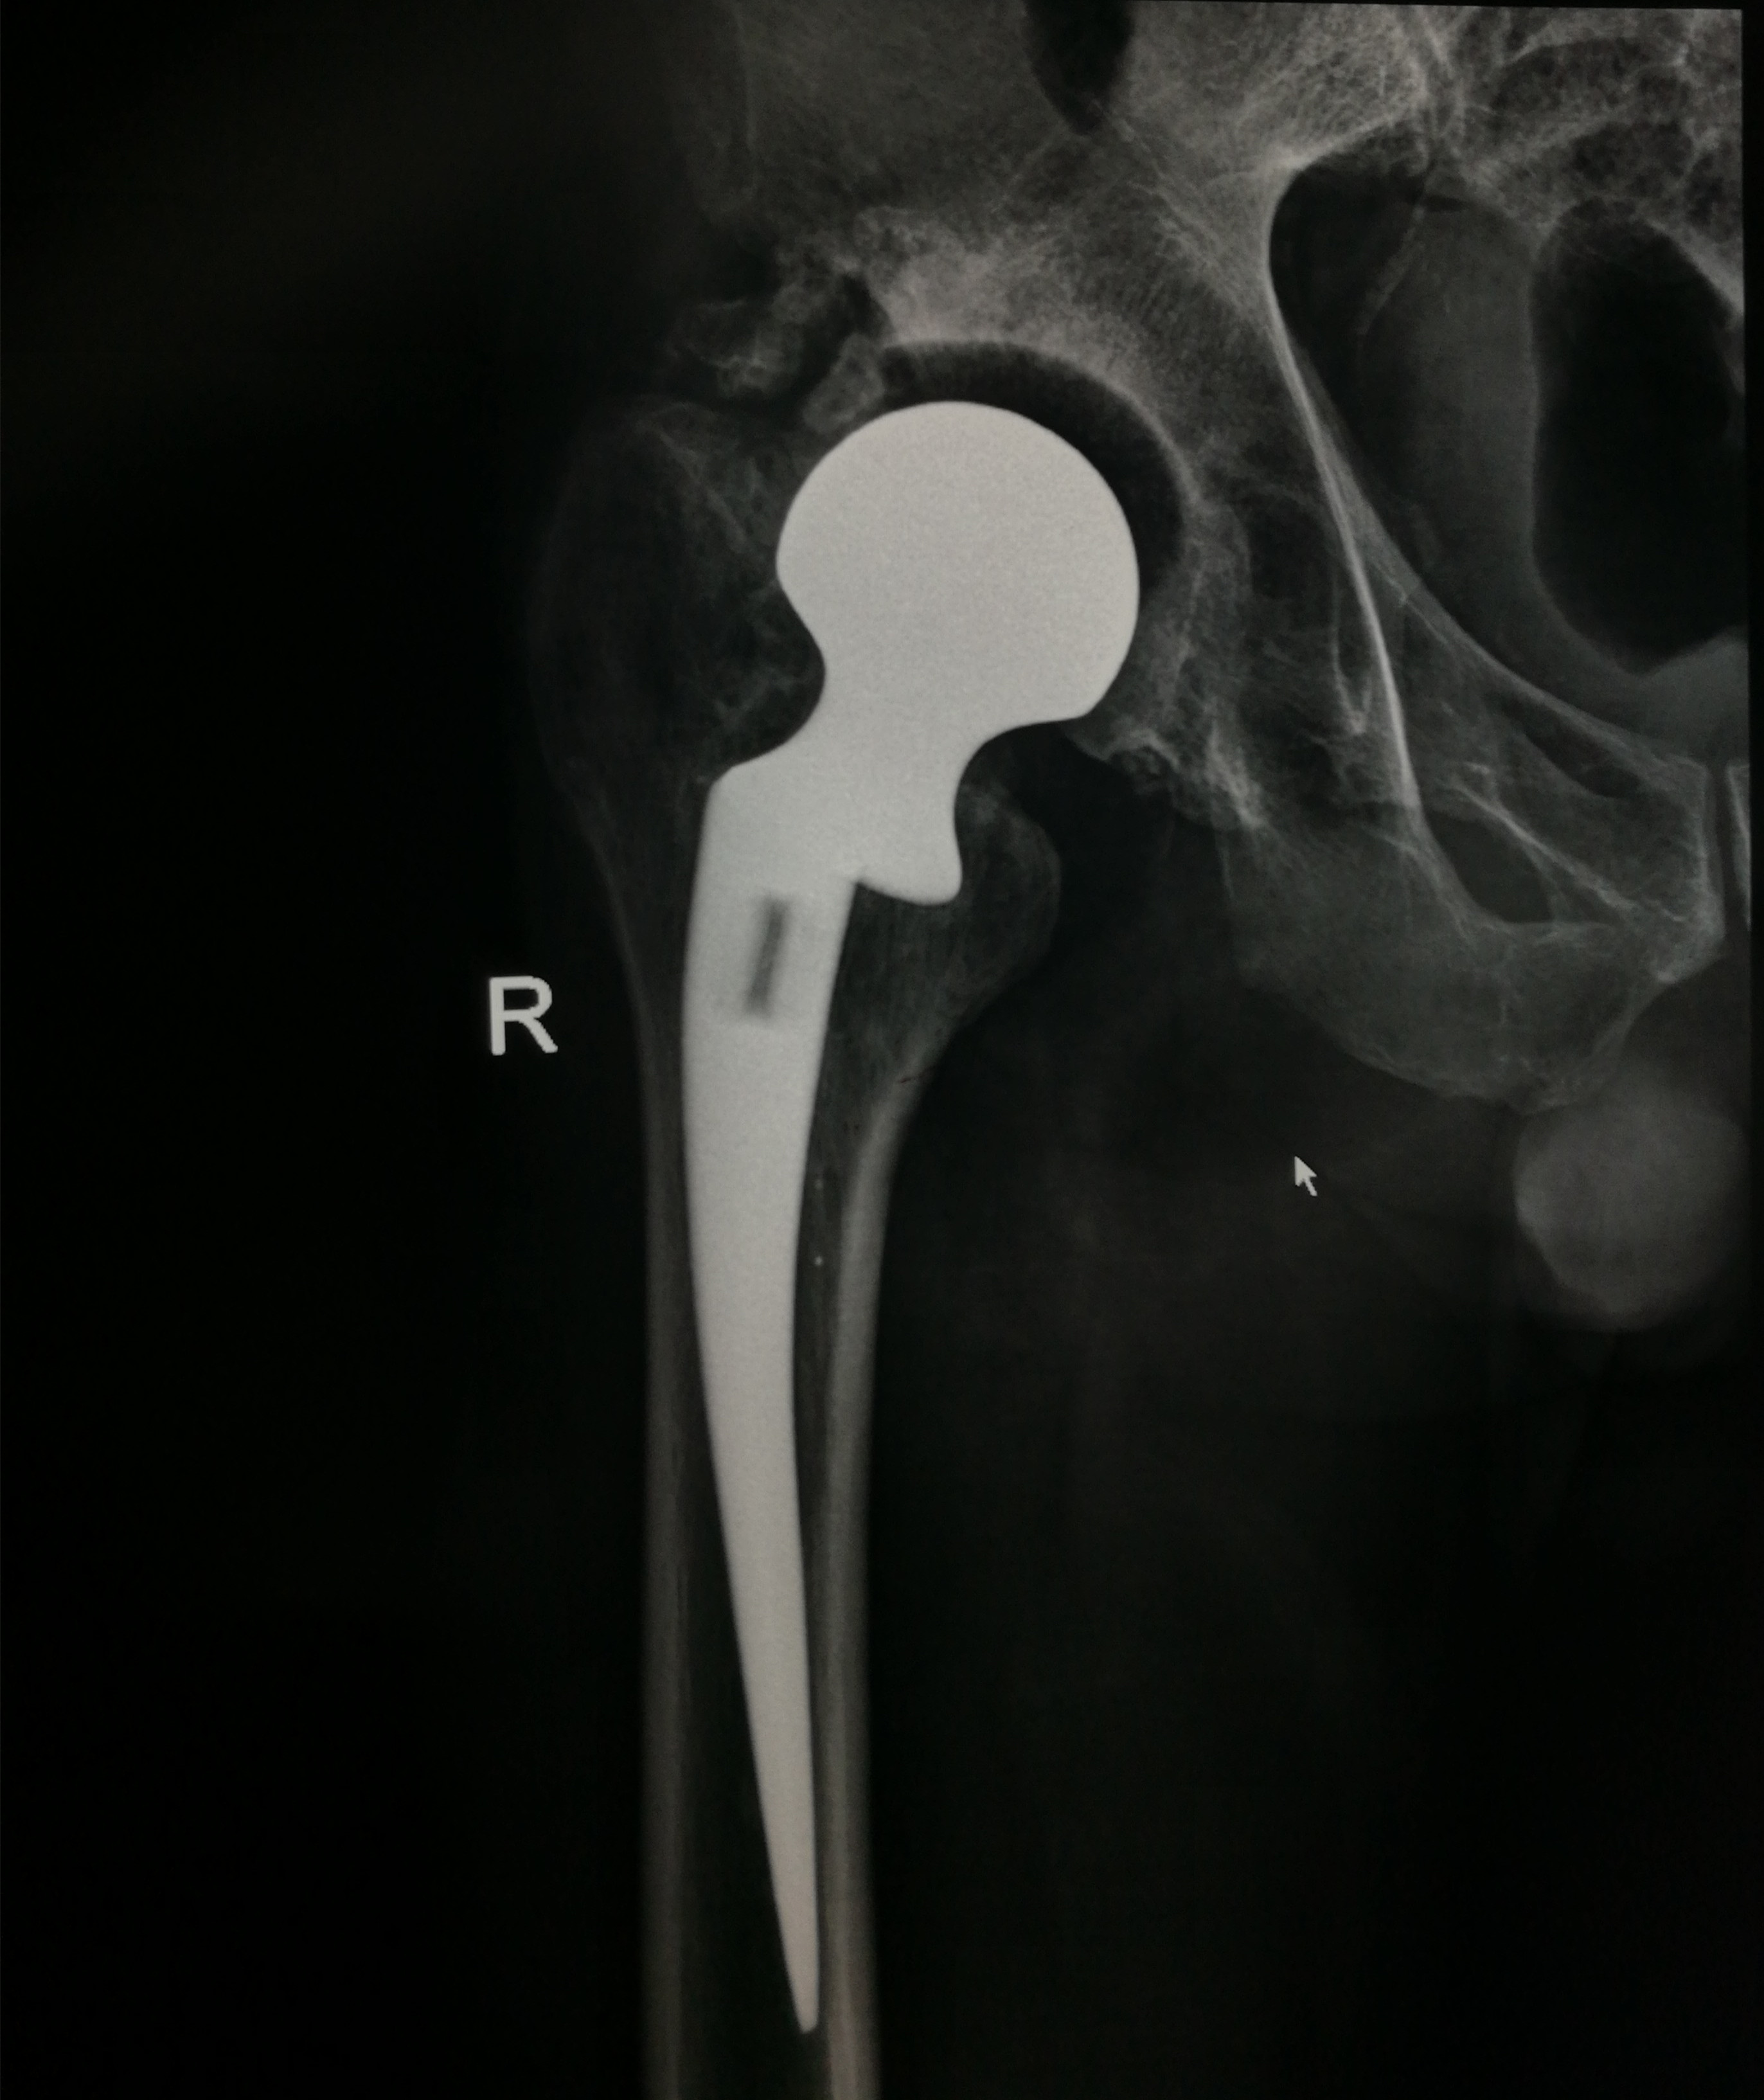

患者王先生,63岁,因半月前不慎摔伤右下肢,在家休息后疼痛加重,遂来我院就诊。骨一科刘波主任接诊后,详细询问其过往病史,得知患者29年前因右侧股骨颈骨折,在济南某医院行右侧人工股骨头置换术,术后右下肢行走良好;但8年前,右髋部疼痛复发、跛行愈加厉害;加之此次摔伤,致使病情加重。经X线检查示:右侧股骨头置换假体下沉,右腓骨远端骨折;且查体后发现其右下肢较左下肢短约5cm。刘主任考虑到王先生年岁已高,且体内假体已有29年,早已超出使用年限,遂决定为其行右侧人工髋关节翻修术。

手术于腰硬联合麻醉下进行,刘主任联合手术医师另行切口,采用钢丝捆绑的方法取出原来关节假体,并重新磋磨髓腔、髋臼,安放新的髋臼假体;随后用骨水泥固定股骨柄假体,并在股骨大转子外侧壁的劈裂骨槽处用接骨板复位坚实固定。术中克服种种不利因素,用时近4个小时,顺利完成右侧髋关节翻修。

术后,刘主任及时为患者量身制定了功能康复锻炼方案,在骨一科医护人员的精心指导下,王先生右下肢功能逐渐恢复。X线检查示:右髋部假体位置良好,力线良好;经术后测量右下肢较左下肢长度相差1cm,基本恢复双下肢等长。术后14天,王先生已能够拄拐下地行走,并顺利拆线出院。该手术的成功标志着我院骨一科在我县骨科临床技术领域获得质的突破。